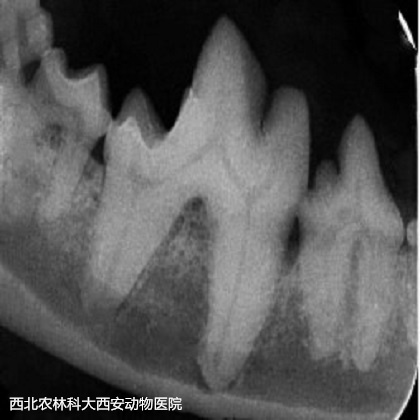

術(shù)前準(zhǔn)備:彈簧開口器撐開口腔,咽部填塞一塊紗布。檢查口腔,可見大量牙結(jié)石見(圖1)。超聲波潔牙術(shù):使用超聲波潔牙器將牙齒的齦上和齦下表面的牙結(jié)石和牙菌斑去除見(圖2)。在潔牙期間發(fā)現(xiàn)其上、下多個(gè)切齒均有松動(dòng),進(jìn)行牙科X線檢查見(圖3),并將上、下切齒各拔掉5顆。108號(hào)齒見(圖4)先前拍片提示存在口鼻瘺,采用注射器噴注可見口腔與鼻腔(右側(cè))連通,使用裂鉆將牙根分開見(圖5),并將牙根分別拔除,口鼻瘺內(nèi)存在多量粘稠惡臭物見(圖6),徹底沖洗口鼻瘺處。牙科手術(shù)刀于上黏膜瓣切出一U形切口,用縫線將黏膜瓣和腭側(cè)黏膜對(duì)合后結(jié)節(jié)縫合見(圖7)。最后,清理口腔去除咽部填塞的紗布?jí)K。術(shù)后通過靜脈輸液給予抗生素和止血藥物。術(shù)后一周每天沖洗口腔兩次,涂抹凝膠四次。一周后回訪恢復(fù)較好,口臭明顯改善,未再出現(xiàn)打噴嚏和流鼻。

圖三

圖四